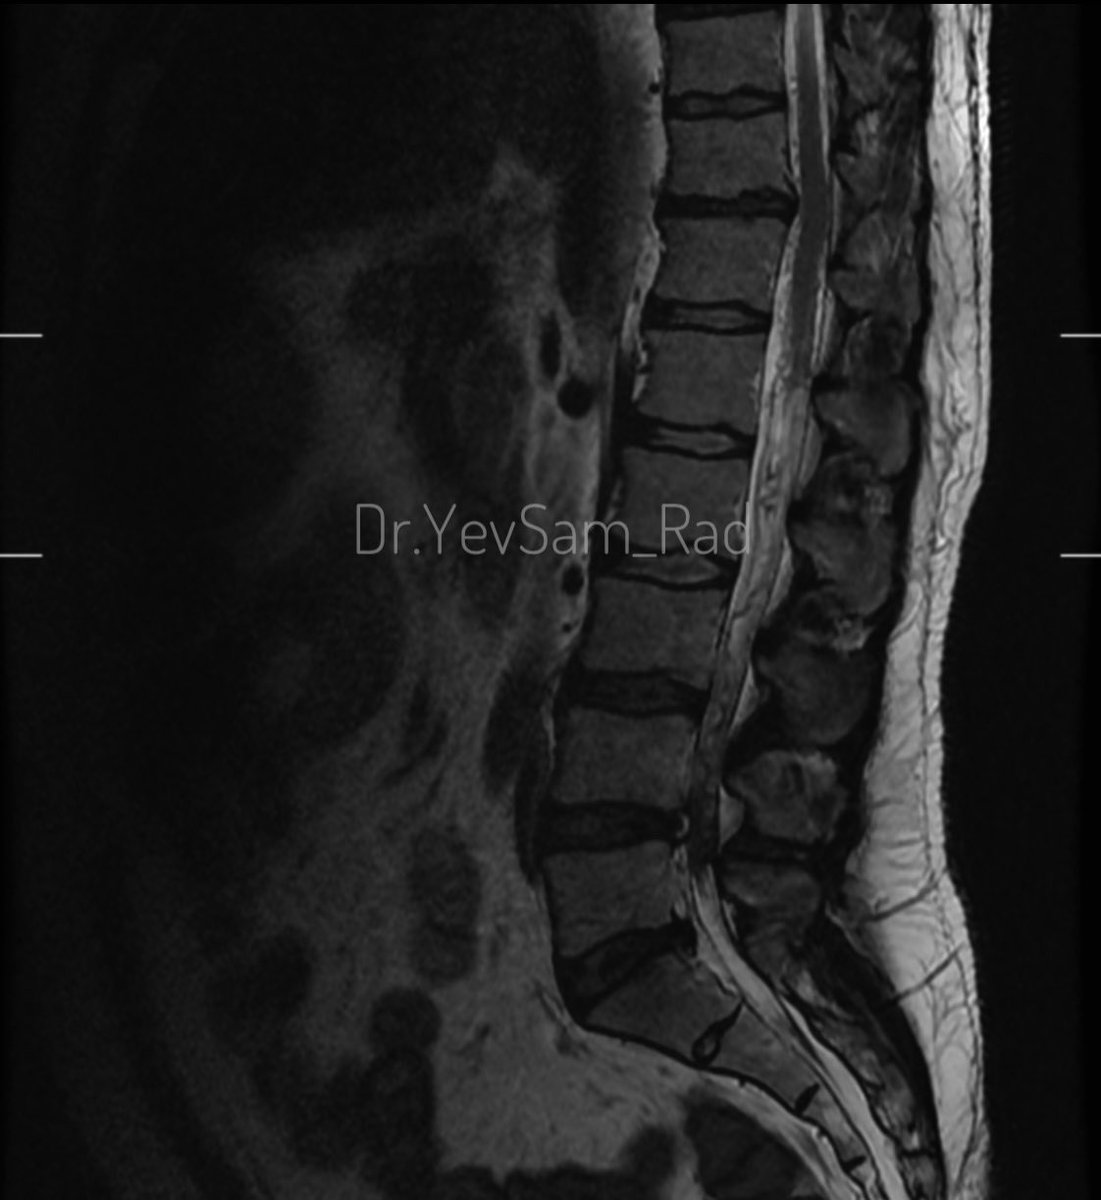

Young gentleman came with severe low back ache following an episode of dengue fever. What do we see here? #spineimaging #medtwitter #radtwitter #FOAMrad #neuroimaging @drvenkimdrd

DrYevSam_Rad's tweet image. Young gentleman came with severe low back ache following an episode of dengue fever. What do we see here?